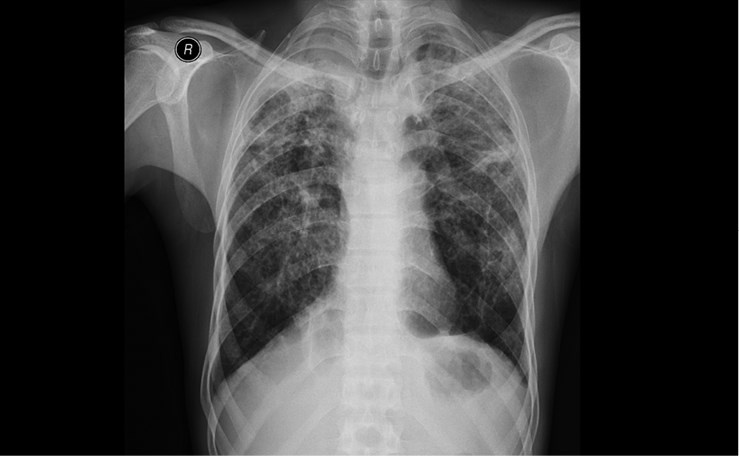

2. Рентгеновский снимок груди одного из молодых людей, занимавшихся пескоструйной обработкой джинсов с 2000 по 2003 г. У них был диагностирован силикоз (осложненный) в 2011 г. Белые зоны на снимке демонстрируют тяжесть заболевания. Изображение любезно предоставлено доктором Метином Акгуном, Университет Аттатюрка

Деним стал одной из самых популярных тканей в мире. Так как его носят мужчины, женщины и дети, деним можно считать повседневной униформой XXI века. В городе Ксинтанг (Китай), джинсовой столице мира, сточные воды после производства двухсот миллионов пар джинсовых брюк, отшиваемых там ежегодно, окрашивают Жемчужную реку в темно-синий и даже черный цвет [627]. Сложный химический коктейль попадает в воду каждый раз, когда появляется новая пара джинсов. Кроме того, начиная с 1970-х годов многие из этих только что выкрашенных синих джинсовых брюк подвергались дополнительной токсичной обработке для придания им состаренного вида. Производители удаляют краситель пятнами или полосами, чтобы создать декоративные «уникальные» следы износа и изобразить патину времени. Техники такого окрашивания включают ручную обработку наждачной бумагой и отбеливание, что вызывает у работников астму. В 1990-х годах была разработана новая технология пескоструйной обработки для «изнашивания» джинсовой ткани, которая в свою очередь изнашивала организмы сотен, а может, и тысяч турецких мужчин. Они работали на установках, обдувающих джинсы абразивным кремнийсодержащим песком, который оставил в их легких неизлечимые шрамы (ил. 2). Турецкие врачи были обескуражены, когда в 2004 году двое подростков погибли от силикоза. Это заболевание распространено у шахтеров и камнеломов и хорошо известно медикам. Но в швейной промышленности эта угроза здоровью рабочих возникла впервые [628]. Специалисты в области профессиональных заболеваний обследовали и опросили мужчин, по 10-12 часов в день 6-7 дней в неделю обрабатывавших деним пескоструйным аппаратом в тесных плохо проветриваемых мастерских Стамбула. Зачастую рабочие и ночевали в том же помещении за занавеской. Мало кому из них достались защитные маски с респираторами, и половина рабочих, участвовавших в обследовании, страдали силикозом [629]. Почти никто из них не получил компенсации. Турецкое правительство запретило эту технологию в 2009 году, но с тех пор ее стали использовать в менее развитых странах с более низким уровнем контроля. Как и другие предметы одежды, описанные в этой книге, многие пары джинсовых брюк все еще хранят на себе как отметины производственного процесса, который их «состаривает», так и уникальный рисунок травм, который эта работа оставила на легких их производителей [630].